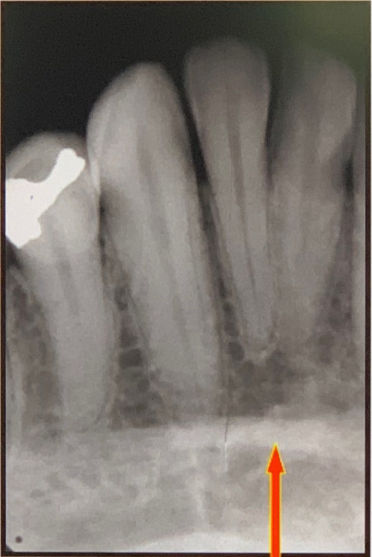

97. What is showing by arrow?

Nutrient Canals: carry a neurovascular bundle and appear as radiolucent lines of uniform width. most often seen on mandibular periapical radiographs running vertically from the inferior dental canal directly to the apex of a tooth or into the interdental space between the mandibular incisors. may appear as a small round radiolucency if they are oriented perpendicular to the cortex.